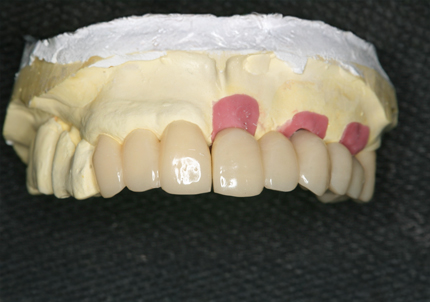

6.インプラントシリンダーテック作製

7.最終補綴作製(前歯部アバットメント装着)

8.ジルコニアフレーム、アバットメント試適

9.セラミック焼成